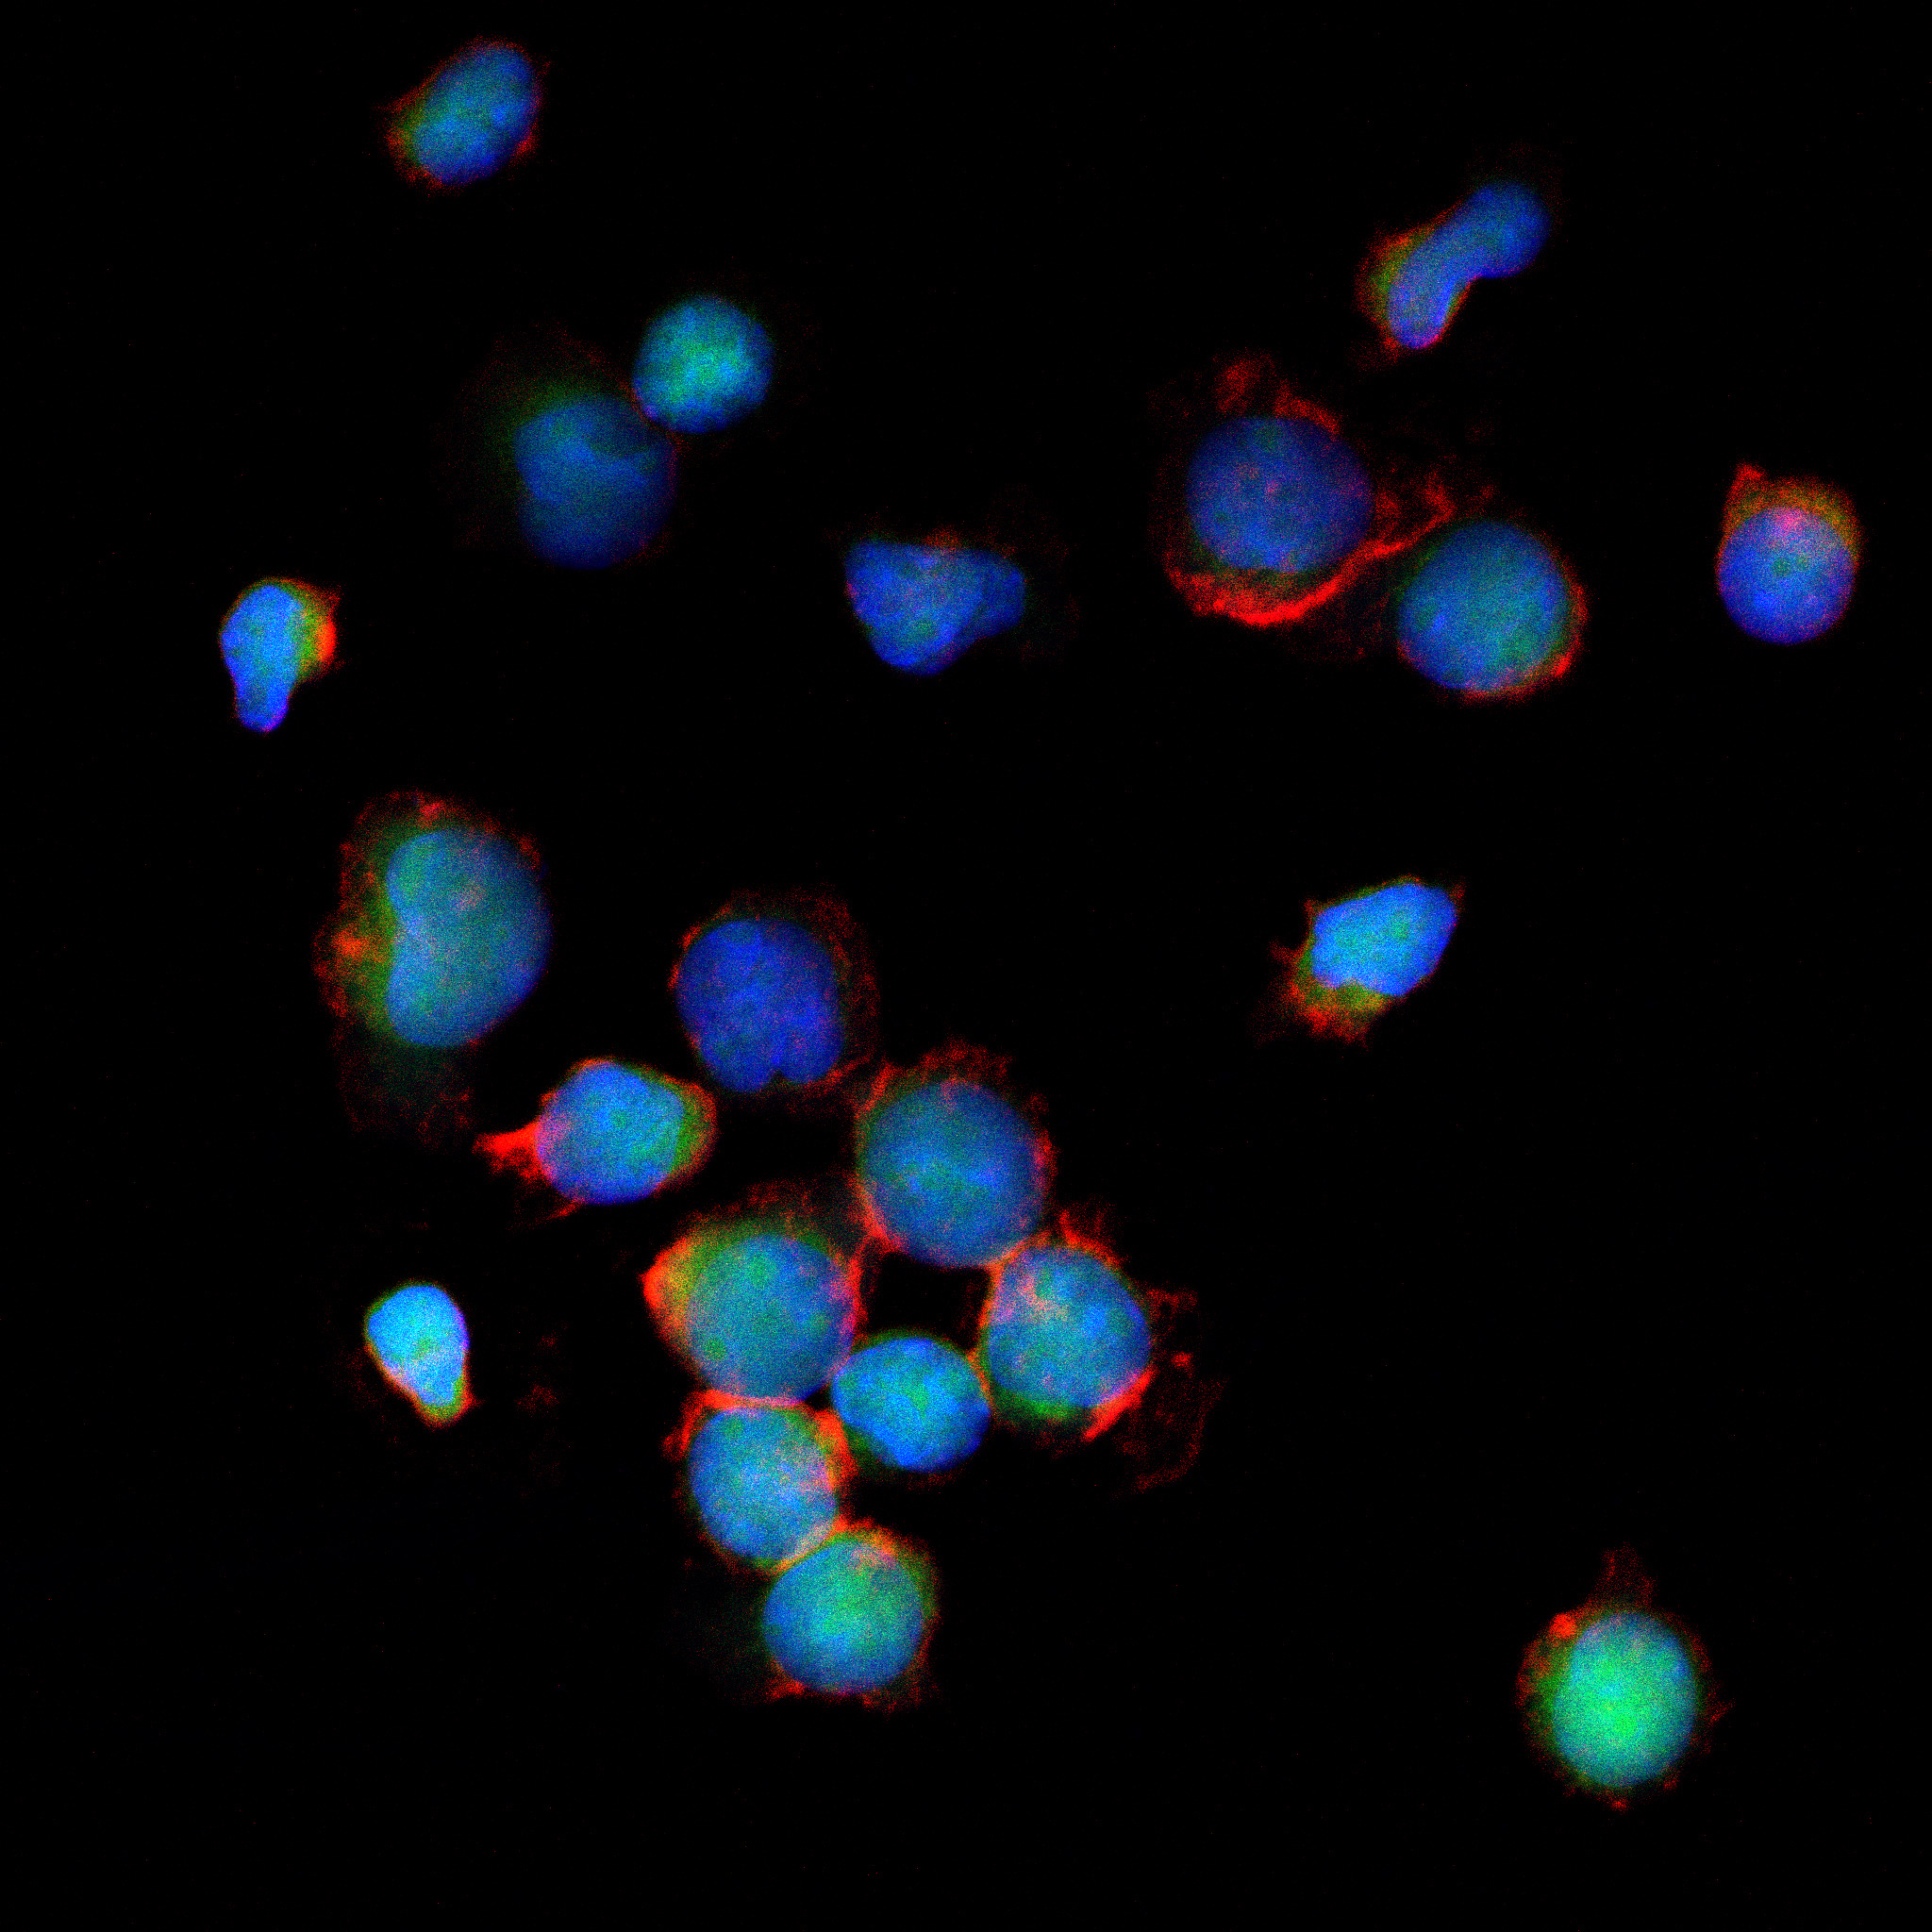

Innowacyjny model finansowania kosztownego leczenia nowotworów złośliwych. Pomysł polega na wykorzystaniu obrazów prawdziwych komórek nowotworowych, przekształceniu ich w dzieła sztuki, a następnie stworzeniu z nich NFT. Pozyskane z akcji środki przeznaczane są na leczenie osób, walczących z przedstawionymi na zdjęciach nowotworami .